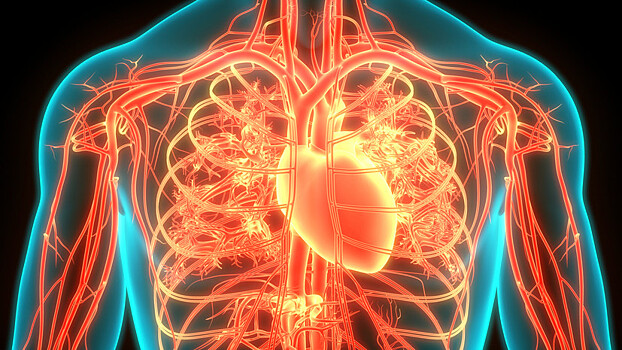

Российские учёные выяснили оптимальный для восстановления сердца возраст стволовых клеток

Российские биофизики определили оптимальный возраст полученных из крови стволовых клеток, во время которого те способны восстанавливать сердечную ткань. Ранее считалось, что необходимо использовать зрелые клетки возрастом от 1 до 2 месяцев. Однако результаты опыта на модели сердца показали, что для омоложения органа лучше всего подходят стволовые клетки с 15 по 28 день созревания. В этом случае они не только прирастают к тканям сердца, но и становятся функциональными, создают единство с сердечными волокнами, отмечают исследователи. Учёные из Московского физико-технического института (МФТИ) и Московского областного научно-исследовательского клинического института им. М.Ф. Владимирского (МОНИКИ) определили, что пригодными для восстановления сердца являются стволовые клетки примерно с 15 по 28 день созревания. Результаты исследования опубликованы в журнале Scientific Reports. В регенеративной медицине для восстановления тканей организма могут использоваться генетически перепрограммированные клетки. Их получают из клеток различных тканей и крови человека. С помощью методов генной инженерии они проходят химическую процедуру дифференцировки, то есть «омоложения» до стволовых клеток (их называют индуцированные плюрипотентные стволовые клетки, или iPS). Они хорошо прирастают к больному органу, но далеко не всегда приступают к восстановлению его тканей. Российские исследователи провели эксперимент на сердечной модели, состоящей из выращенной ткани этого органа. Клетки для опытов были предоставлены Национальным медицинским исследовательским центром им. академика Е.Н. Мешалкина (Новосибирск). По ткани пускали волны возбуждения, согласованно распространяющиеся по волокнам и имитирующие сокращение сердца. Учёные использовали модель как инструмент проверки качества iPS-клеток, полученных в разное время. Результаты эксперимента выявили так называемое «окно возможности» — оптимальный для подсаживания к органу возраст стволовых клеток, способных к омоложению ткани. Лучшими для пересадки оказались iPS-клетки в возрасте от 15 до 28 дней. «Мы обнаружили, что те клетки, которые подсаживали после 28-го дня от начала дифференцировки, использовать уже нельзя, потому что они не объединяются с сердечной тканью. Они к ней прирастают, но они не функциональны, не создают единства с сердечными волокнами», — пояснил руководитель проекта, заведующий лабораторией биофизики возбудимых систем МФТИ Константин Агладзе. Исследование позволяет наиболее эффективно использовать iPS-клетки. Ранее ошибочно считалось, что для этого подходят более зрелые клетки — возрастом от 1 до 2 месяцев, отмечают учёные.